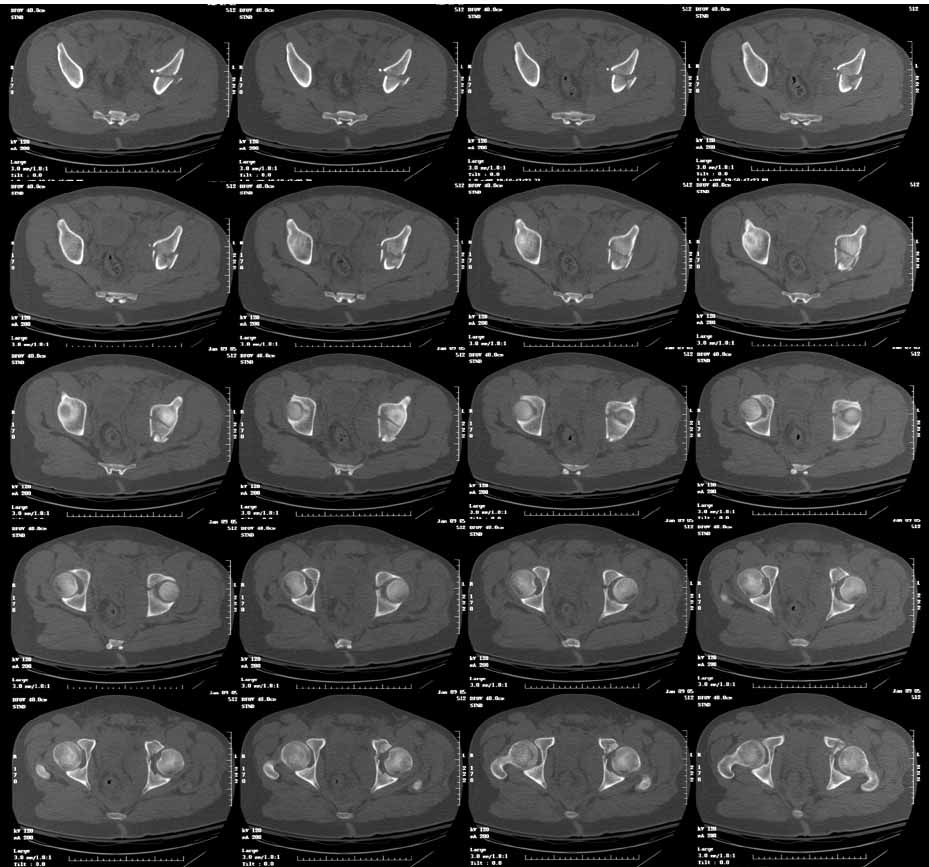

This is an 18 yo male involved in an MVA 2 days ago. Isolated injury other than some rib fxs. I had trouble interpreting the xrays, but the CT shows a both column fracture with secondary congruence (I think). The plain films show significant gapping of the anterior column, but the CT shows fairly little at the dome.

Yes, the posterior column dominant fracture fragment will follow the anterior column. Some surgeons would concentrate on the articular reduction and tolerate the slight residual medial displacement of the hip from the intact ilium. Both can be improved.

You'll notice by CT that there is an intact labral "hinge" which usually indicates that these 2 dominant articular fragments will behave together intraop. But you'll still need to expose, clean, and clamp them before fixation. And your operative goal is to have the articular reduction be perfect on the postop CT...can you make this one better?

The consequences of letting it heal as is are unknown but I'll tell you this...many postop CT scans don't look as good thru the dome as his does PREOP! You should really understand what you have and what you will do to improve it...maybe that's why you sent it, eh?

You'll notice that the anterior column is incomplete peripherally...this lends stability if you elect to treat him without surgery, and indicates an osteotomy at the iliac crest to complete the fracture and allow its mobilization for cleaning and reduction, should you choose surgery.

In my opinion, he will do well treated nonoperatively, and I have many similar cases in my practice with favorable followup. As Chip points out, the anterior column is incomplete peripherally, thus very stable in its current position. These are very hard to move intra operatively until the fracture is completed. Nonoperative Rx does carry a slight chance of further displacement, so close followup is needed. If I did anything operative, it would be a perc screw from anterior to posterior to secure the dome reduction. This can be done using the iliac wing view that profiles the "teardrop" to target the screw.